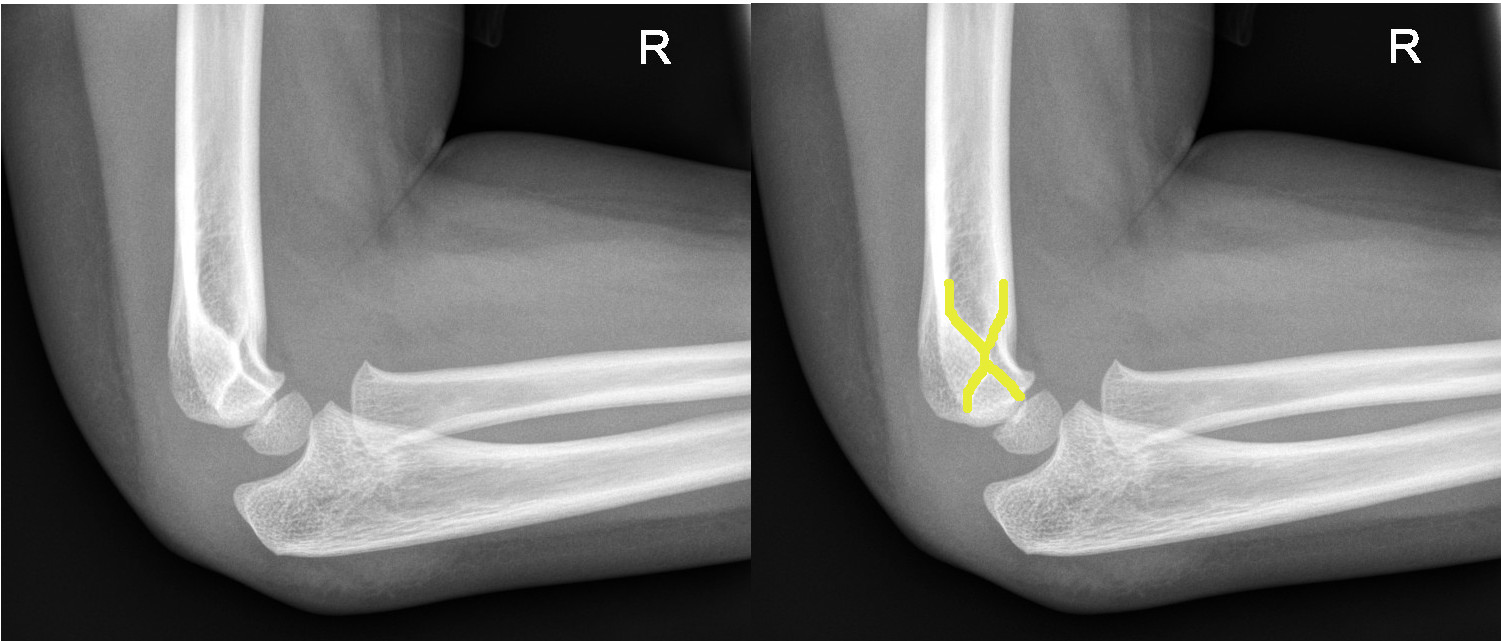

6. Look for obvious fracture lines on the AP view

|

Supracondylar fracture evident on the AP view |